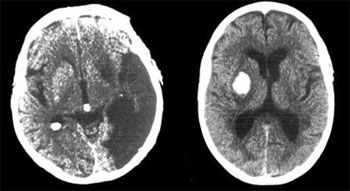

CT einer Hirnblutung (rechts)

und einer Mangeldurchblutung

(links) im späteren Stadium

Zunächst erfolgt eine neurologische Untersuchung, bei der die neurologischen Ausfallserscheinungen festgestellt, den betroffenen Gehirnregionen zugeordnet und andere Ursachen ausgeschlossen werden. Zur Unterscheidung zwischen einer Mangeldurchblutung („Ischämie“) und einer Blutung dient die Computertomographie (CT).

Moderne Geräte erlauben eine Schichtaufnahme des Gehirns (Röntgenaufnahme) in wenigen Minuten. Eine Blutung lässt sich unmittelbar nachweisen, während die Durchblutungsstörung im frühen Stadium (innerhalb der ersten 24 Stunden) einen unauffälligen Befund liefern kann. Unter Umständen kann eine Kernspintomographie (MRT) des Gehirns sinnvoll sein.